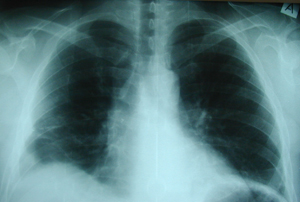

Περίπτωση Νο 2

Εικόνα 1

Οπισθιοπροσθία ακτινογραφία θώρακος στην οποία φαίνεται ότι υπάρχει ευμεγέθης όγκος που προβάλλει δεξιά παρακαρδιακά.